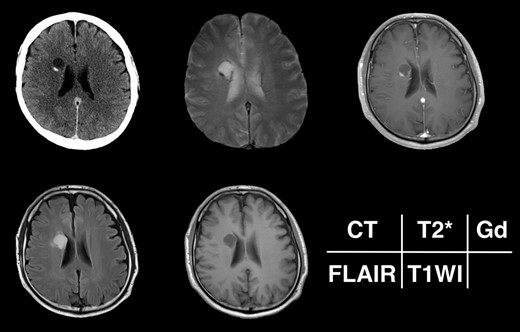

Radiological appearance of the lesion on CT and MRI. The lesion appears as a hypodense cyst with hyperdense nodules in the periventricular region on CT. Both the cystic wall and nodule show signal hypointensity on T2*-weighted images and Gd-enhancement on contrast-enhanced T1-weighted images. The cyst is hyperintense on FLAIR and hypointense on T1-weighted images.

Given the absence of neurological symptoms, the patient was followed conservatively. After a follow-up period of 10 years, the lesion started to increase in size from 10 to 18 mm, accompanied by worsening of headaches. MRI revealed that the increased size of the lesion was attributable to an enlargement of the cystic component and the mural nodule (Fig. 1). A cystic mass with a gadolinium (Gd)-enhancing cyst wall and mural nodule were present. Signal intensity of the cystic component was high on T2-weighted imaging and fluid-attenuated inversion recovery (FLAIR) imaging. The cyst wall and nodule showed low signal intensity on T2*-weighted imaging (Fig. 2). Surgical removal was performed via a trans-cortical approach achieving gross total removal. The cystic component was covered with a transparent thin membrane containing clear yellow fluid, while the mural nodule comprised white, tough tumorous tissue. The lesion showed no invasion into the lateral ventricle. The postoperative course was uneventful, with no complications. No headache and no sign of recurrence have been seen, as of 13 months after surgery (Fig. 2).